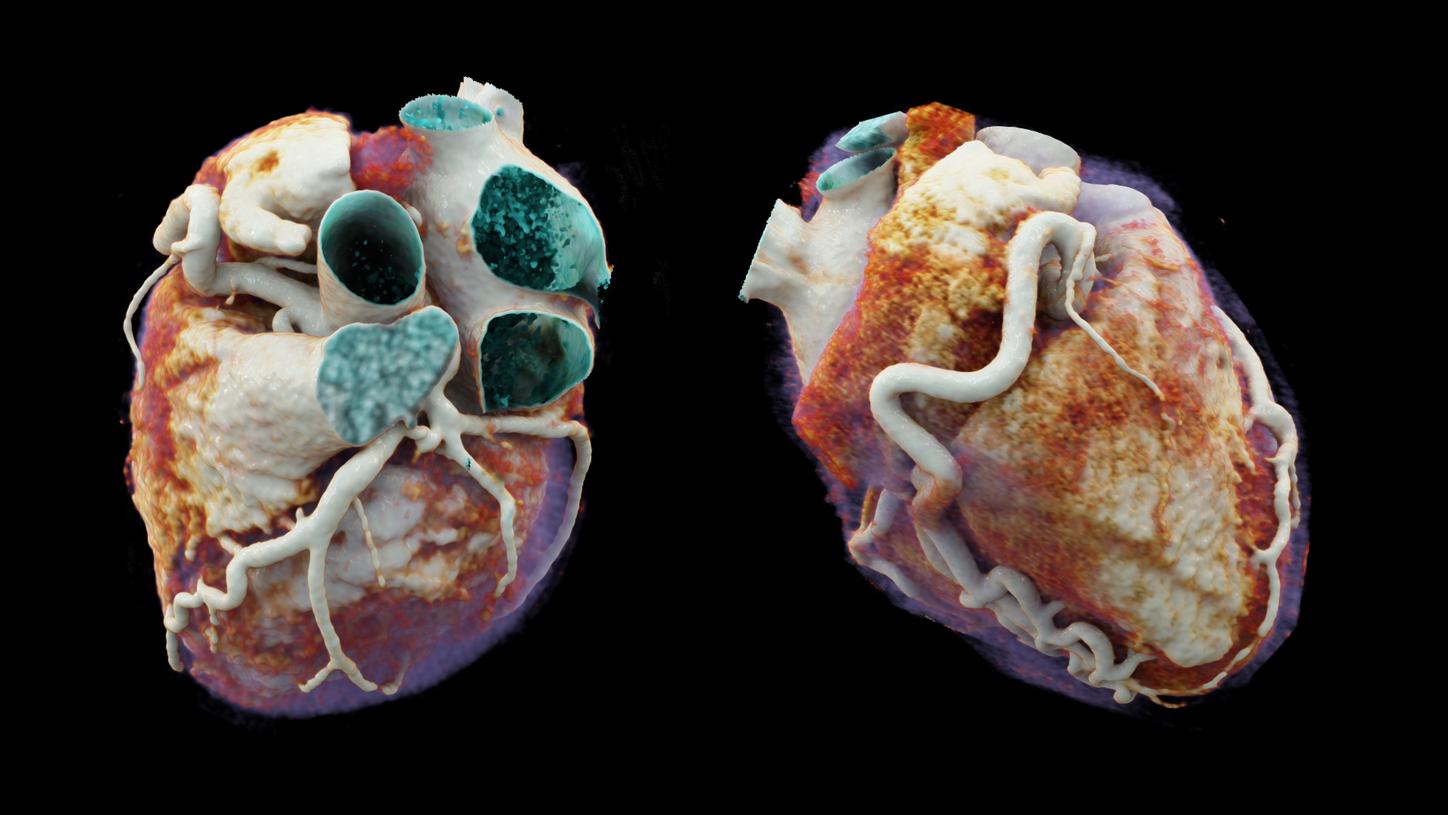

Computed Tomography is moving beyond its traditional diagnostic role to become a key player in early disease detection and therapy planning. This

expansion means an even broader patient cohort and resilient productivity demands. You need a reliable partner with products, services, and the

infrastructure to support new business models and prioritize environmental sustainability and robustness. Computed Tomography at Siemens Healthineers,

with its legacy of listening for almost 50 years, is innovating ahead of these developments, even before potentials become needs.